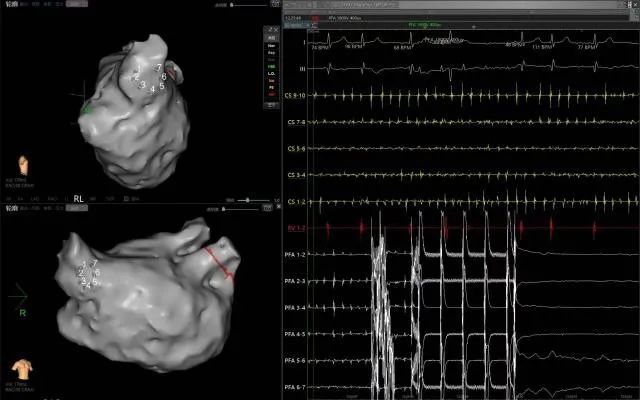

近日,延安大學(xué)咸陽醫(yī)院成功實(shí)施了咸陽地區(qū)首例脈沖場消融術(shù)、首例脈沖場消融+左心耳封堵“一站式”治療房顫手術(shù)2例手術(shù)的順利完成,標(biāo)志著我院在心律失常治療技術(shù)上的又一重大突破!

此次手術(shù)患者均為持續(xù)性房顫患者,由延安大學(xué)咸陽醫(yī)院吳棟梁院長、心律失常專家劉雄濤副院長帶領(lǐng)介入團(tuán)隊(duì)開展,安全高效、圓滿完成手術(shù),手術(shù)過程患者全程清醒,術(shù)中自訴感覺良好,無痛苦感受。術(shù)后患者的心律恢復(fù)并維持了竇律,目前恢復(fù)情況良好,無任何并發(fā)癥出現(xiàn)。